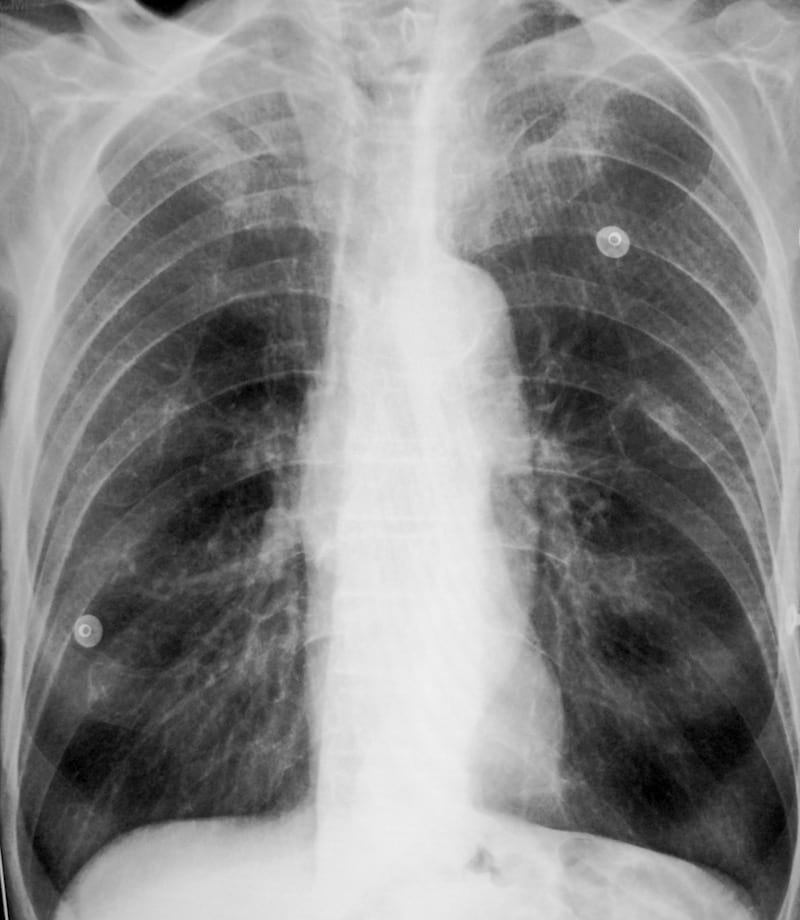

75-year old smoker presenting with acute dyspnoea and productive cough. Describe the ECG.